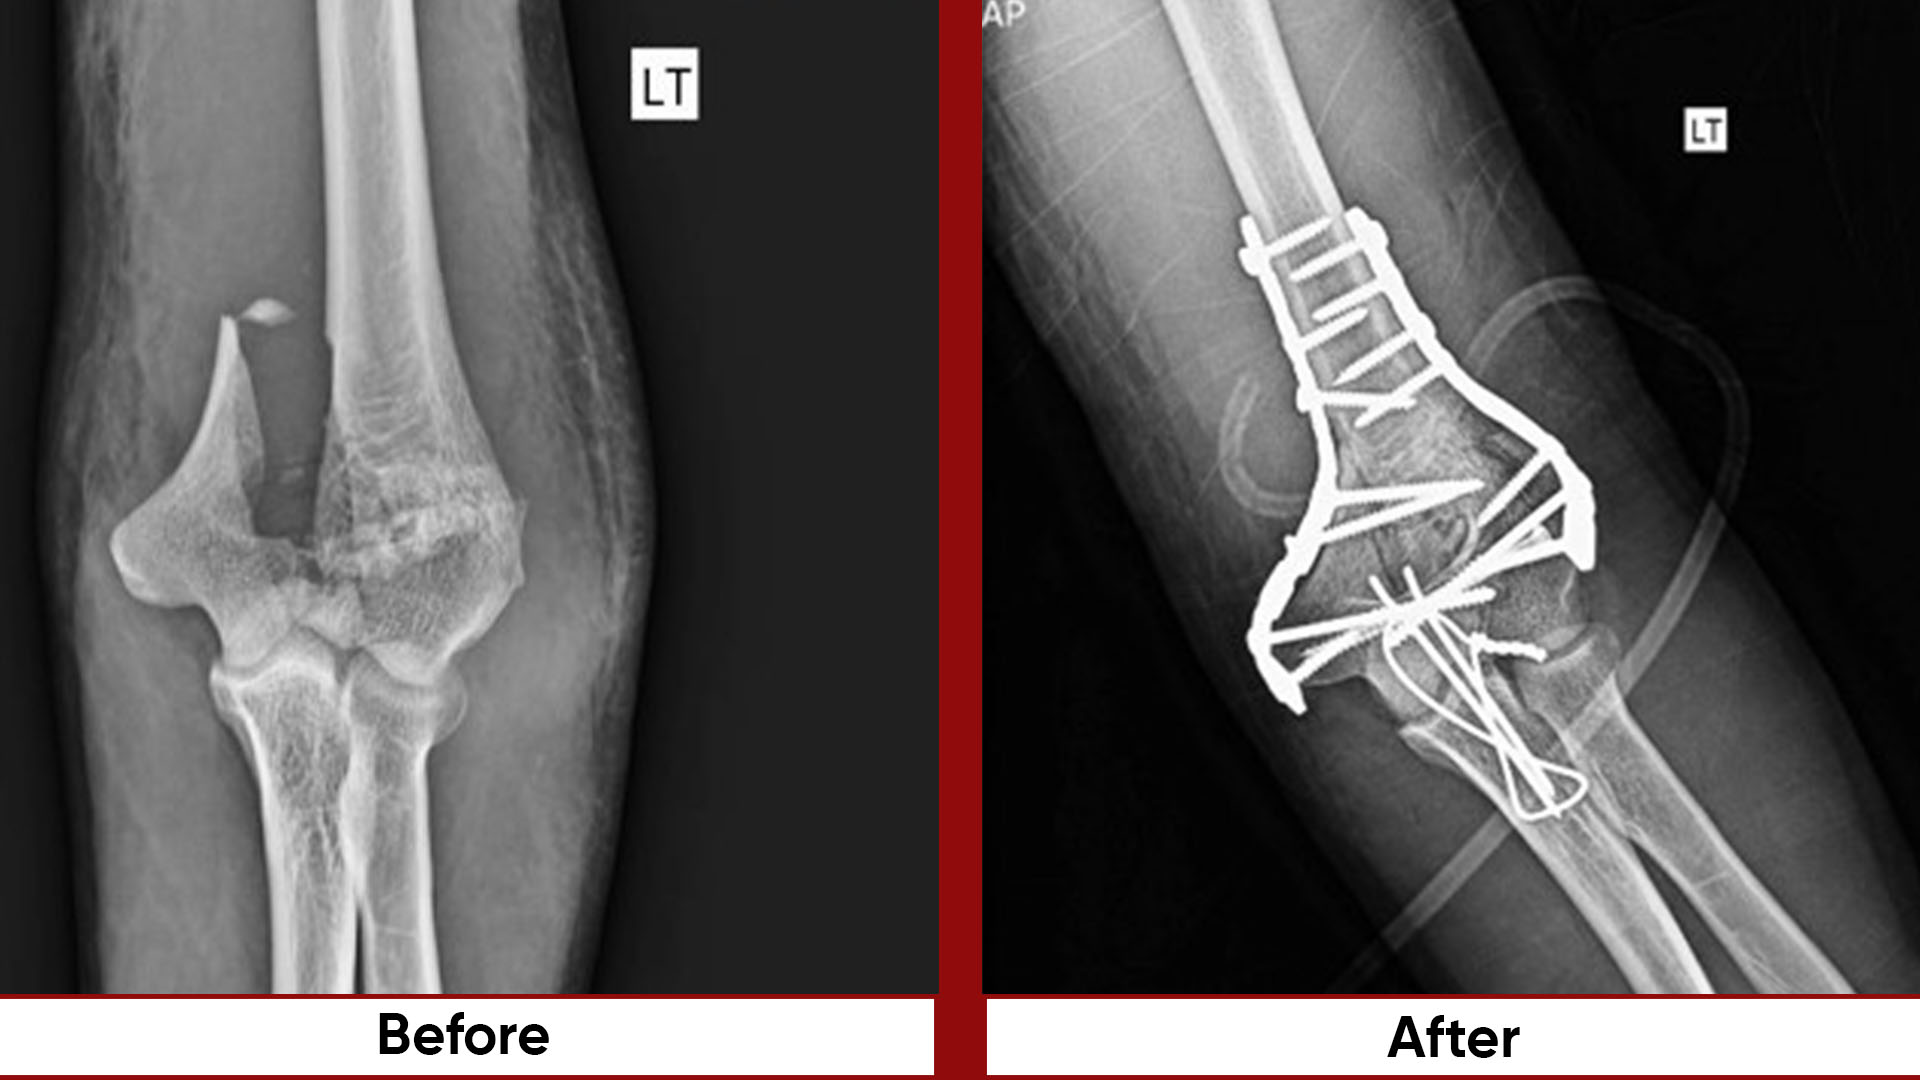

• Fracture Management (simple and complex trauma)

• Arthroscopic Surgeries (Knee & Shoulder)